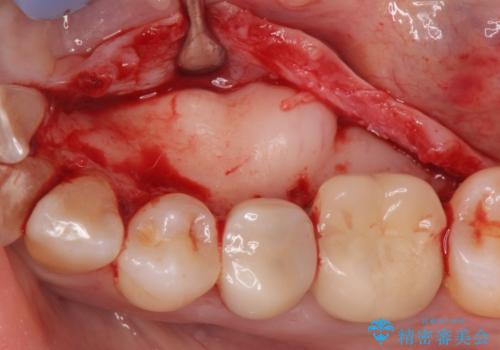

骨隆起除去

- 骨隆起が舌にあたり不快感があるので骨隆起をとりたくて来院。

静脈内鎮静麻酔下で骨隆起を除去を行いました。